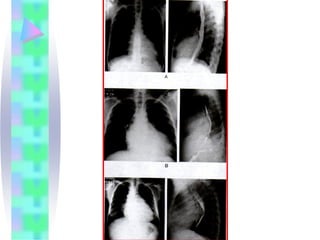

Radiologia

• Problemas que podem ser sugeridos ou

diagnosticados pelo RX de tórax

•   ICC

•   Edema Pulmonar

•   Derrame Pleural

•   Hipertensão Pulmonar Severa

•   Malformações Congênitas

•   Shunt esquerda-direita

•   Doença Cardíaca Valvar

•   Pericardite construtiva calcificada

•   Grandes Derrames Pericárdicos

•   Cisto pericárdico

•   Miocardiopatia

•   Sobrecarga das câmaras cardíacas

Radiologia • Problemas quepodem ser sugeridos ou diagnosticados pelo RX de tórax • ICC • Edema Pulmonar • Derrame Pleural • Hipertensão Pulmonar Severa • Malformações Congênitas • Shunt esquerda-direita • Doença Cardíaca Valvar • Pericardite construtiva calcificada • Grandes Derrames Pericárdicos • Cisto pericárdico • Miocardiopatia • Sobrecarga das câmaras cardíacas